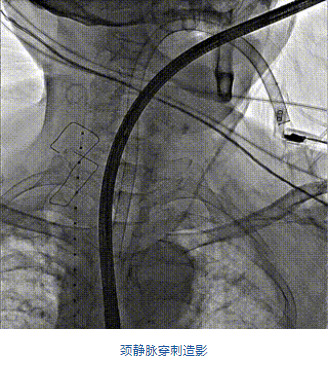

團隊前期經過多次討論,制定了周密的手術策略和預案。由于患者已是近九旬的超高齡老人,傳統(tǒng)外科開胸手術風險極高,純介入經血管三尖瓣替換能夠明顯減少創(chuàng)傷。術中陳茂及馮沅教授結合體表定位在造影指示下精準穿刺右側頸靜脈并預置兩把血管縫合器。成功建立經皮血管入路后在食道超聲和DSA的引導下順利完成人工瓣膜植入,術后超聲和造影顯示人工三尖瓣同軸性良好,瓣架固定牢靠,無反流和瓣周漏,平均跨瓣壓差降為1mmHg。術畢收緊預置的血管縫合器縫線完成止血,縫合效果滿意,在手術室即刻拔除氣管插管。